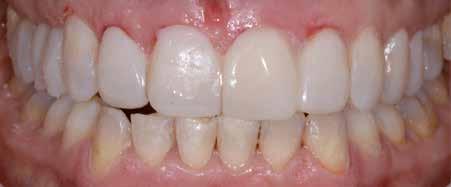

Hölgy páciensem az első konzultáció során tipikus kórtörténetet vázolt fel: Gyermekkora óta szeretett volna fogszabályozó készüléket, hiszen mindig is zavarta a class 2-es eltérésnél tipikusan jellemző nagy overjet (1-3. képek), és természetesen az ezáltal kifelé álló felső metszőfogai, részben a felső metszők protrúziója, részben pedig a disztálisan elhelyezkedő mandibula miatt. Annak ellenére, hogy több fogszabályozó szakorvosnál is járt az évek során, de mivel saggitális eltérése és az alsó metszőfogak torlódása miatt négy kisőrlőfog extrakcióját, illetve emellett sokszor állcsont műtétet is javasoltak neki, nem vágott bele a kezelésbe (4-5. képek).

A fogorvosa – nagyon helyesen – felhívta a figyelmét, hogy parodontális státusza is valószínűsíthetően romlani fog az eltérése miatt, újabb kört futott, immár 39 évesen, de még mindig premoláris fogak húzása és állcsontműtét nélkül szerette volna a fogszabályozást.

A konzultáció során arról is beszéltünk – ahogy az ilyenkor lenni szokott –, sohasem szeretett igazán mosolyogni, de a Pitts Protokolloknak köszönhetően az arc- és mosolyesztétikai céloknak megfelelően kerül megvalósításra az okklúziós korrekció. Az okklúziós kezelési célok az alábbiak voltak: a felső és alsó fogív nivellálása és tágítása, az alsó fogsor/ mandibula mezializálása, valamint a harapás megemelése által a mélyharapás rendezése.

A fogkontúrálás és az interproximális redukció alkalmazásával a mikroesztétikai részletek tökéletesítése is megtörtént (11. kép) A kezelés mindössze 16 hónapig tartott, megtörtént a rágófunkció helyreállítása, és az esztétikai végeredmény sokéves várakozás után valóban fordulópontot jelentett páciensünk életében (12-14. képek).